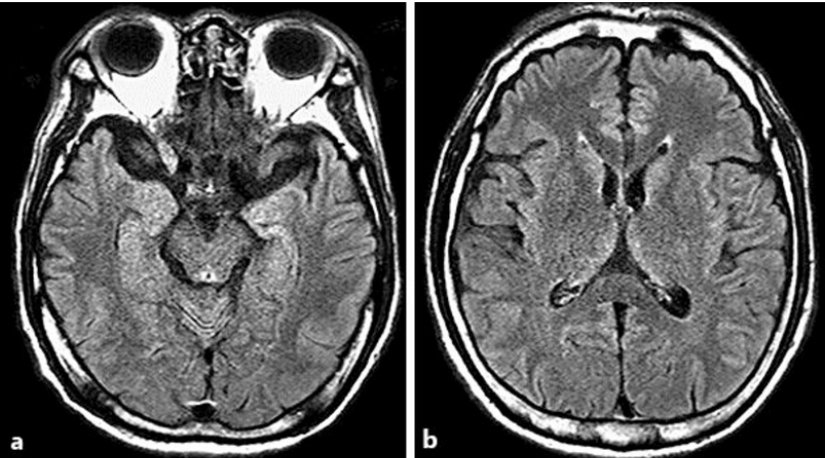

Manyetik Rezonans Görüntüleme (MRI) ve Bilgisayarlı Tomografi (CT) gibi yöntemler, beynin yapısal durumunu inceleyerek retrograd amneziye yol açabilecek nörolojik anormalliklerin belirlenmesini sağlar. Manyetik Rezonans Görüntüleme, beyin dokusundaki hasarları, tümörleri veya dejeneratif süreçleri detaylı bir şekilde görüntülerken Bilgisayarlı Tomografi, genellikle travmaya bağlı beyin hasarlarını tespit etmek için tercih edilir. Fakat bu yöntemlerin her zaman hafıza kaybının kesin nedenini ortaya koyamayacağı unutulmamalıdır.

Yapısal incelemelerin ötesine geçen ve beyin aktivitelerini değerlendiren Pozitron Emisyon Tomografisi (PET) ile Fonksiyonel Manyetik Rezonans Görüntüleme (fMRI) gibi ileri teknikler, beynin belirli bölgelerindeki işlevsel değişiklikleri gözlemleme imkânı tanır. Bu tür yöntemler özellikle retrograd amneziye neden olan nörolojik değişimleri daha ayrıntılı bir biçimde analiz etme açısından faydalıdır.